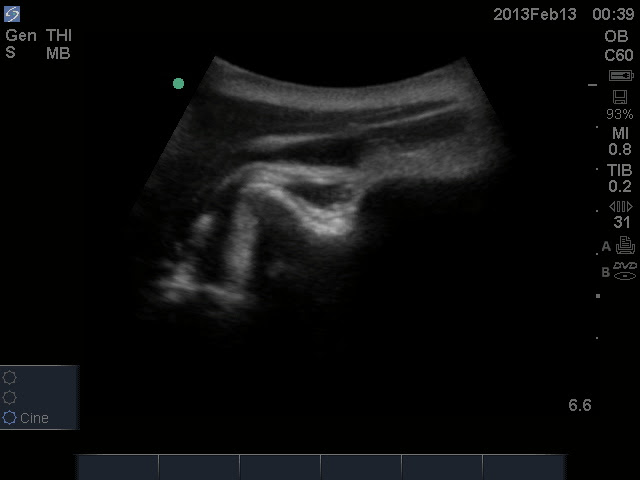

US-guided closed reduction of a R anterior shoulder dislocation

Before (glenoid and humeral head in yellow, supraspinatus tendon in red)

After (glenoid and humeral head in yellow, supraspinatus tendon in red)